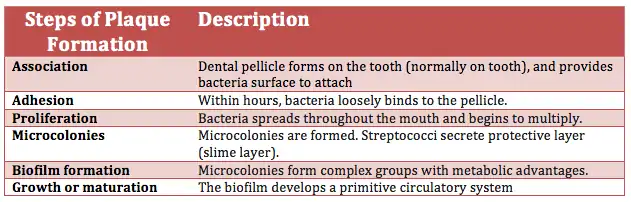

Plaque formation

Dental plaque is a biofilm that attaches to tooth surfaces, restorations and prosthetic appliances (including dentures and bridges) if left undisturbed. Understanding the formation, composition and characteristics of plaque helps in its control.[5] An acquired pellicle is a layer of saliva that is composed of mainly glycoproteins and forms shortly after cleaning of the teeth or exposure of new teeth.[6] Bacteria then attach to the pellicle layer, form micro-colonies, and mature on the tooth, which can result in oral diseases. The following table provides a more detailed (six-step) explanation of biofilm formation: